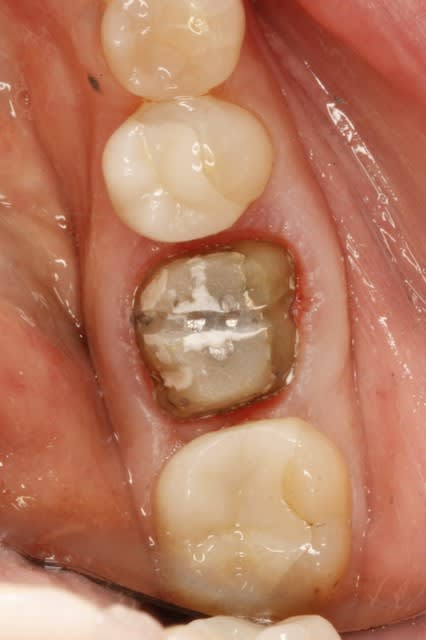

Ci-joint, compo trouvé sous une CCM avec 3 paraposts,

fait il y a plus de 24 ans (1987), et non, pas par moi,

je suis trop jeune.

J'ai placé les 2 onlays (5 et 7) il y a 10 ans.

J'ai collé une e-max par dessus le vieux compo+parapost, il y a quelques mois.

Donc, faut croire que c'est possible de faire du compo sous des couronnes...depuis 20 ans, voir plus .